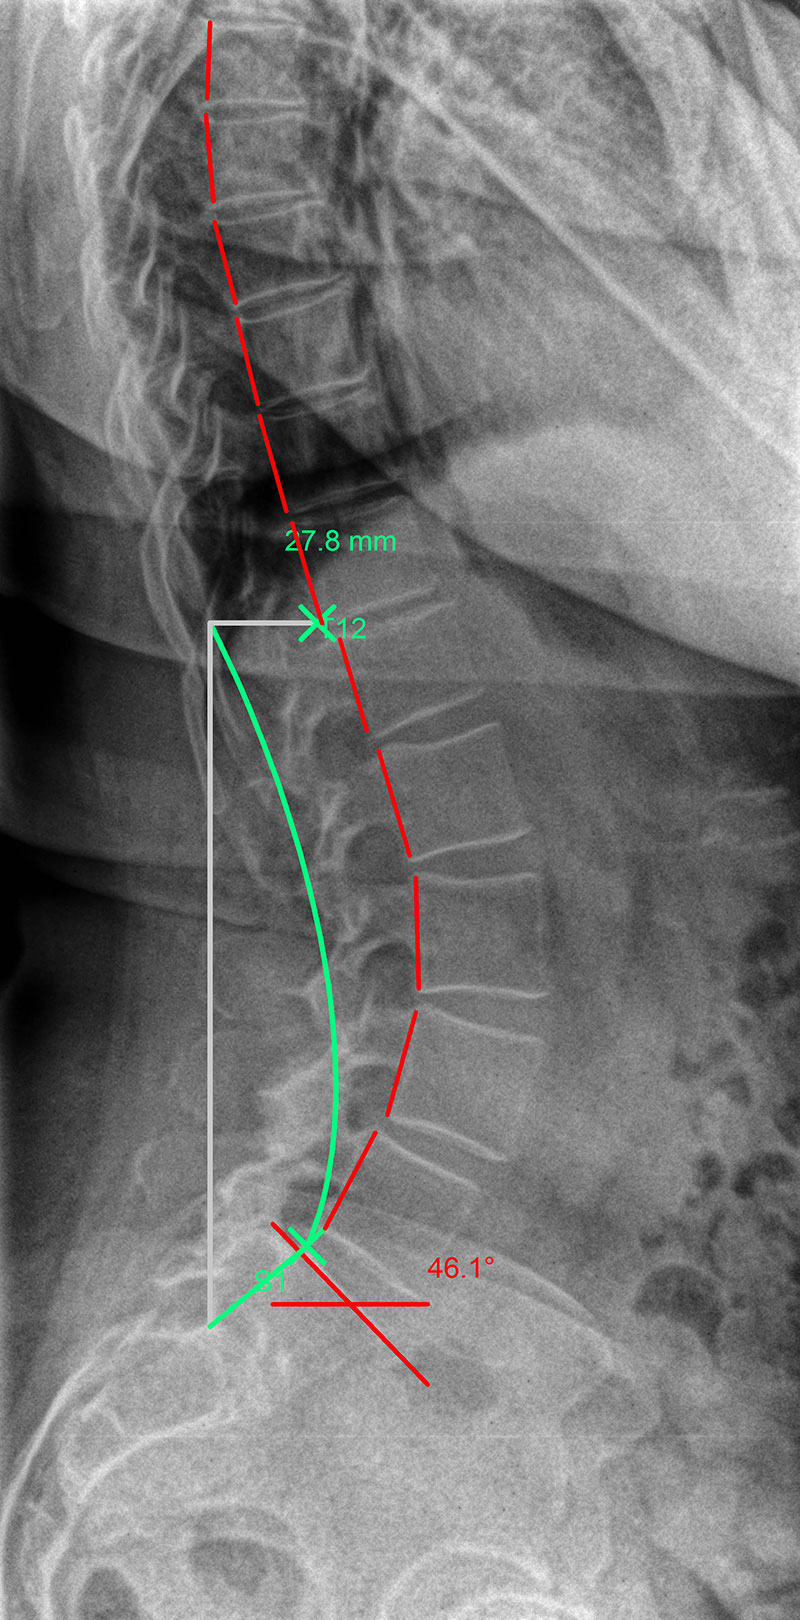

Hypolordosis: |

The green line represents the ideal spinal curvature and the red line that of the patient’s spine in profile view.